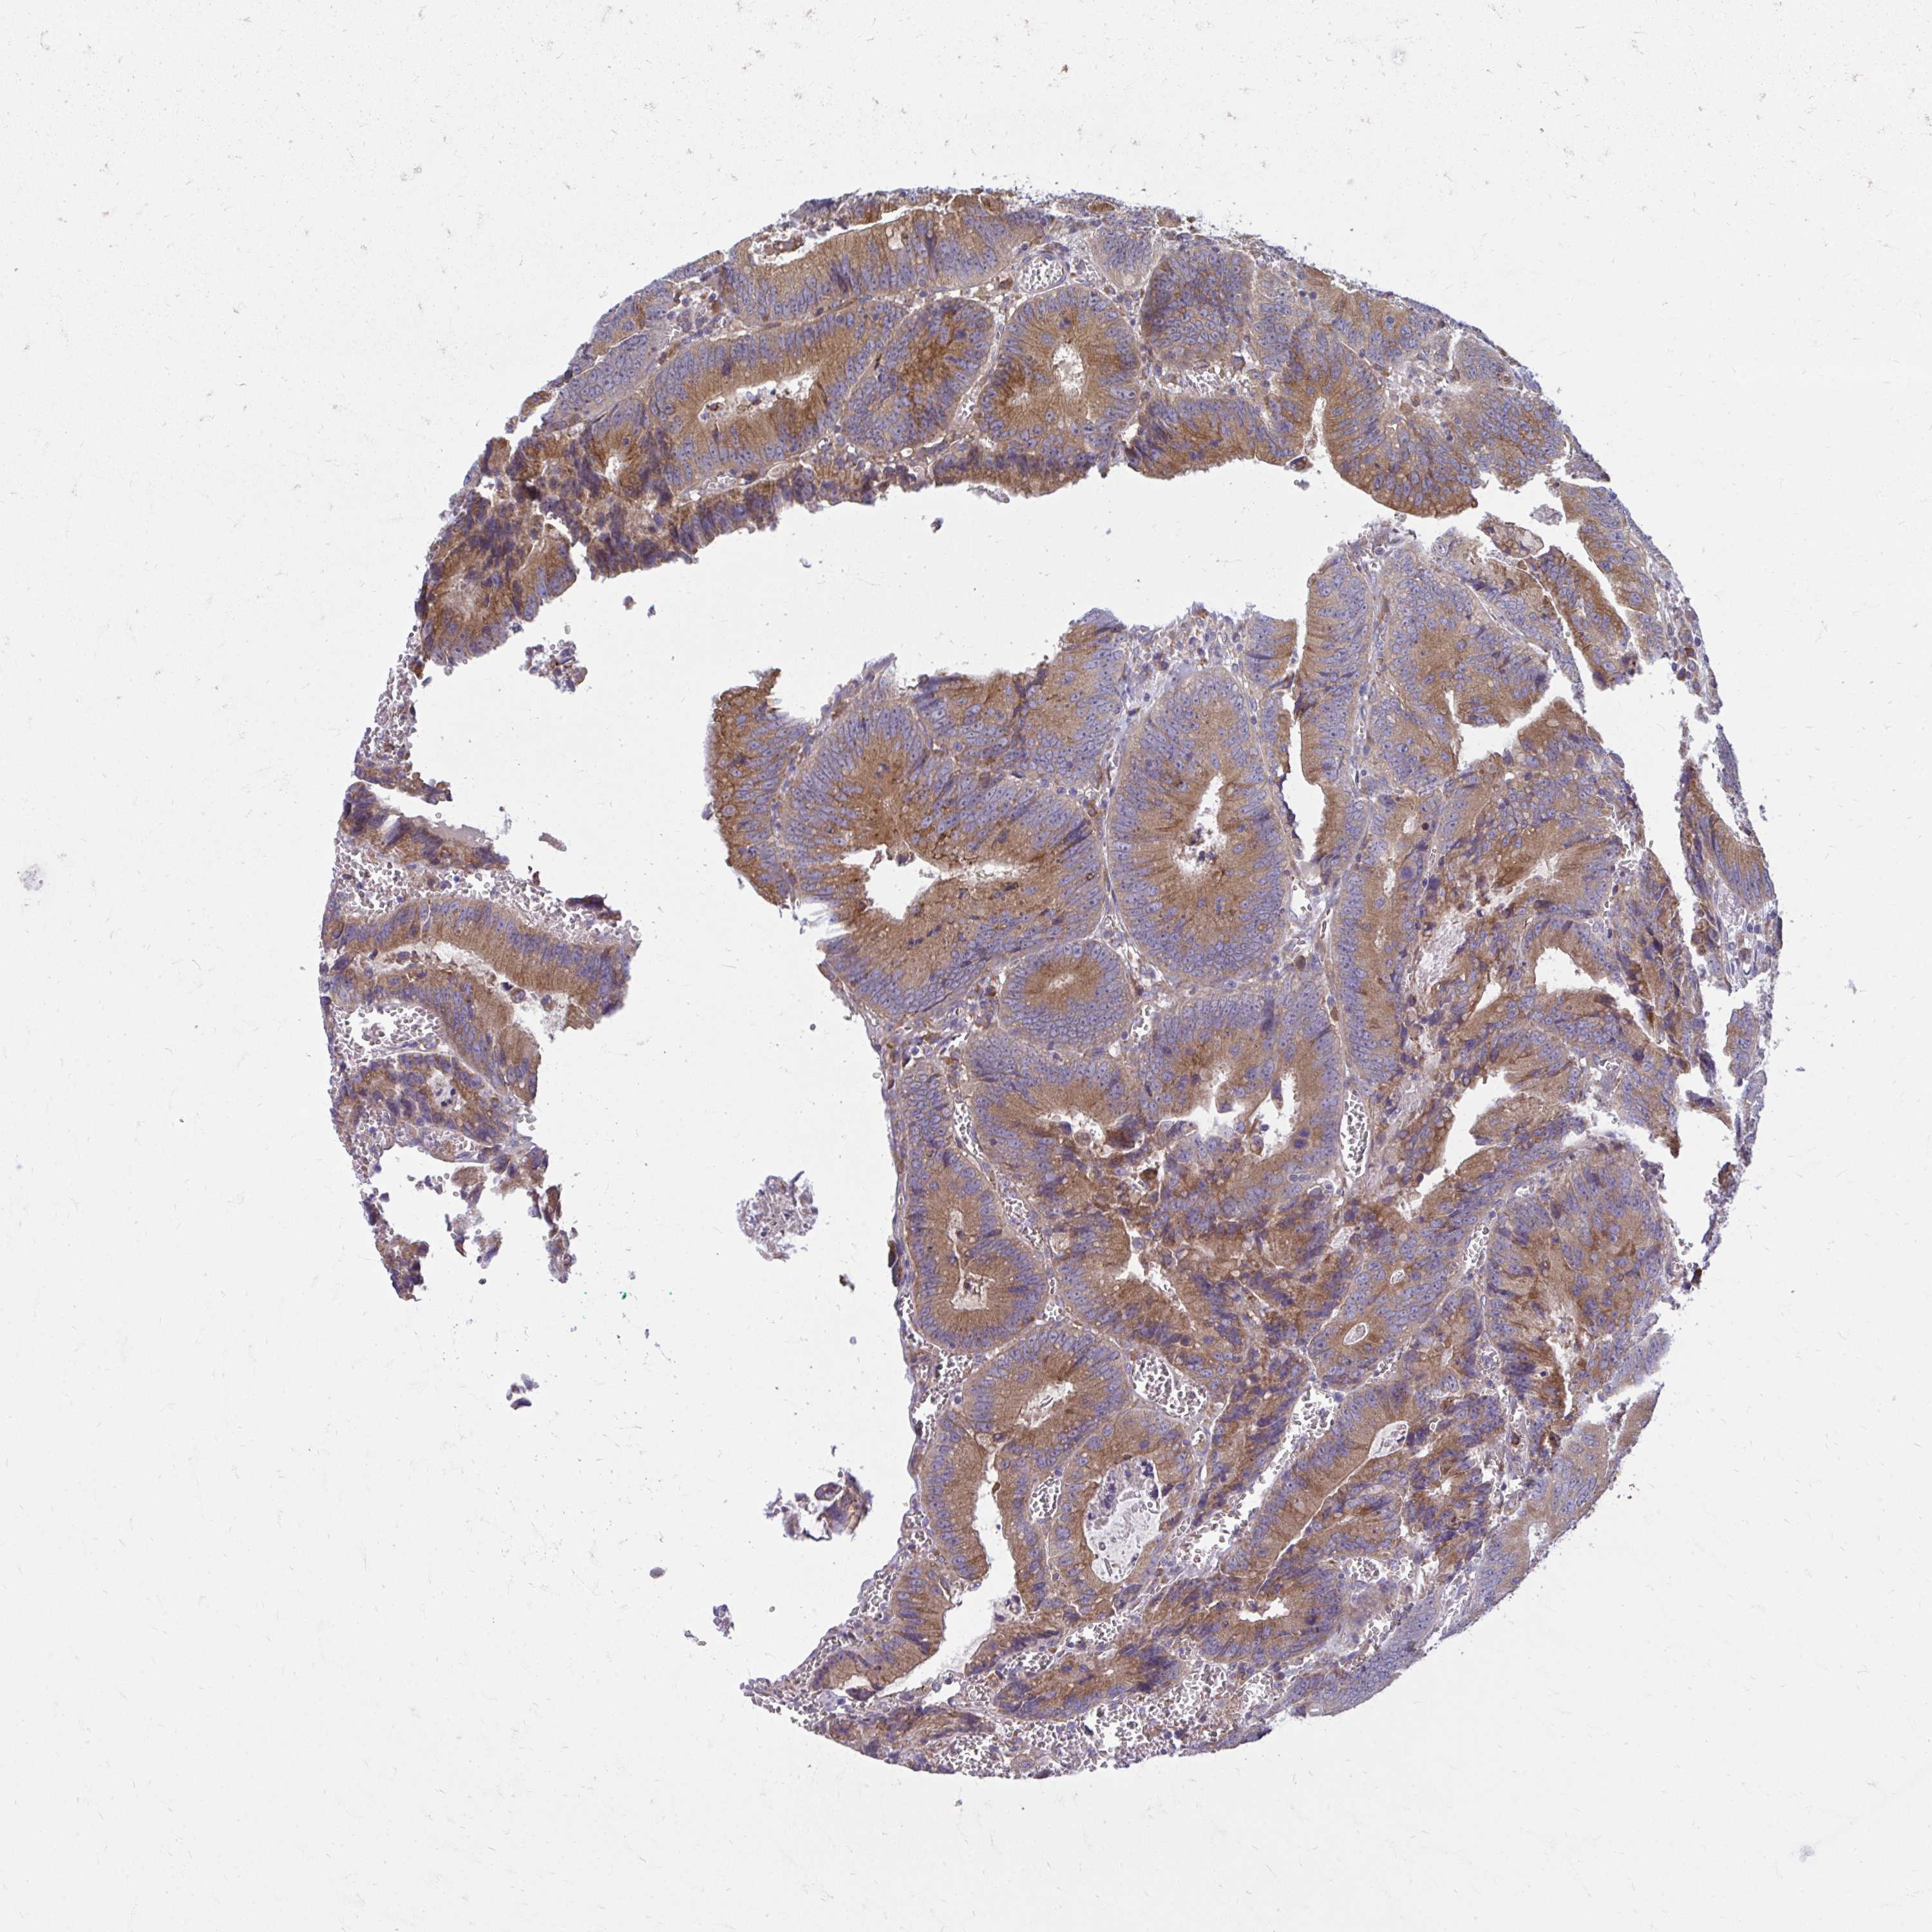

CANCER COLORECTAL CANCER Show tissue menu

Colorectal cancer

Human cancer

Colon adenocarcinoma